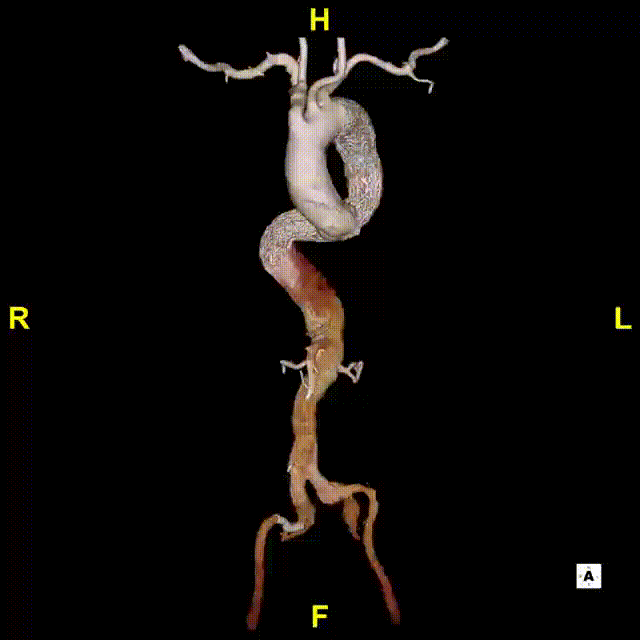

3D影像

3)LSA起始部平均直径43mm+,降主段多发破口,真腔狭窄。